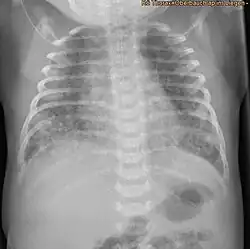

Thorax-Röntgenbild eines weiblichen Neugeborenen (1 Tag alt) mit Mekoniumaspiration

Durch das eingeatmete Mekonium entstehen in der Lunge des Kindes Bereiche mit unzureichender Belüftung (Atelektasen), während andere Bereiche dagegen überdehnt bzw. überbläht (Lungenemphysem) werden. Bei der Überblähung wirkt das in den Atemwegen befindliche zähe Mekonium wie ein Ventil. Atemgas wird bei der Überdruckbeatmung zwar am Mekonium vorbei in die nachgeschalteten Lungenbläschen eingeblasen, kann aber bei der Ausatmung nicht mehr am Mekonium vorbei entweichen und verbleibt in der Lunge. Die betroffenen Lungenbezirke können nicht mehr ausreichend ausatmen und werden so überbläht. Die Folgen eines solchen ungleichmäßigen Belüftungsverhaltens einzelner Lungenbereiche sind in der Röntgenaufnahme der Lunge (Röntgen-Thorax) deutlich zu sehen. Der Radiologe befundet ein „Mischbild aus diffuser Minderbelüftung (Atelektasen) bei gleichzeitig vorhandenen Bereichen der Überblähung (Emphysem)“. Sehr häufig tritt in einer solchen Situation ein Pneumothorax auf. Die sehr dünne Membran der überdehnten Lungenbläschen zerreißt und Atemgas gelangt dann aus den Alveolen in das Lungen-Bindegewebe (interstitielles Emphysem). Findet diese außerhalb der Alveolen gelegene Gasansammlung dann Anschluss an den Pleuraspalt, wird dort die Haftung der beiden Pleurablätter aufgehoben und die Lunge zieht sich auf Grund der Eigenelastizität zusammen. Hierdurch kann eine akut lebensbedrohliche Situation für das Kind resultieren. Als weitere Komplikation der Mekoniumansammlung in den Atemwegen entsteht eine reaktive Pneumonie (Lungenentzündung) und eine Inaktivierung von lungenstabilisierendem Faktor (Surfactant). Während bis vor 15–20 Jahren ein MAS noch eine schwer zu behandelnde Erkrankung des Neugeborenen mit hoher Sterblichkeit darstellte, sind die Behandlungsergebnisse des MAS heute durch spezielle Beatmungstechniken, antibiotische Therapie, inhalative Stickoxidtherapie (iNO) und vor allem der Gabe von aus Tierlungen extrahiertem lungenstabilisierendem Faktor (Surfactantsubstitution) erheblich verbessert worden. So ist der ECMO-Bedarf bei Neugeborenen mit diesem Krankheitsbild über die letzten 10 Jahre kontinuierlich gesunken.[6]